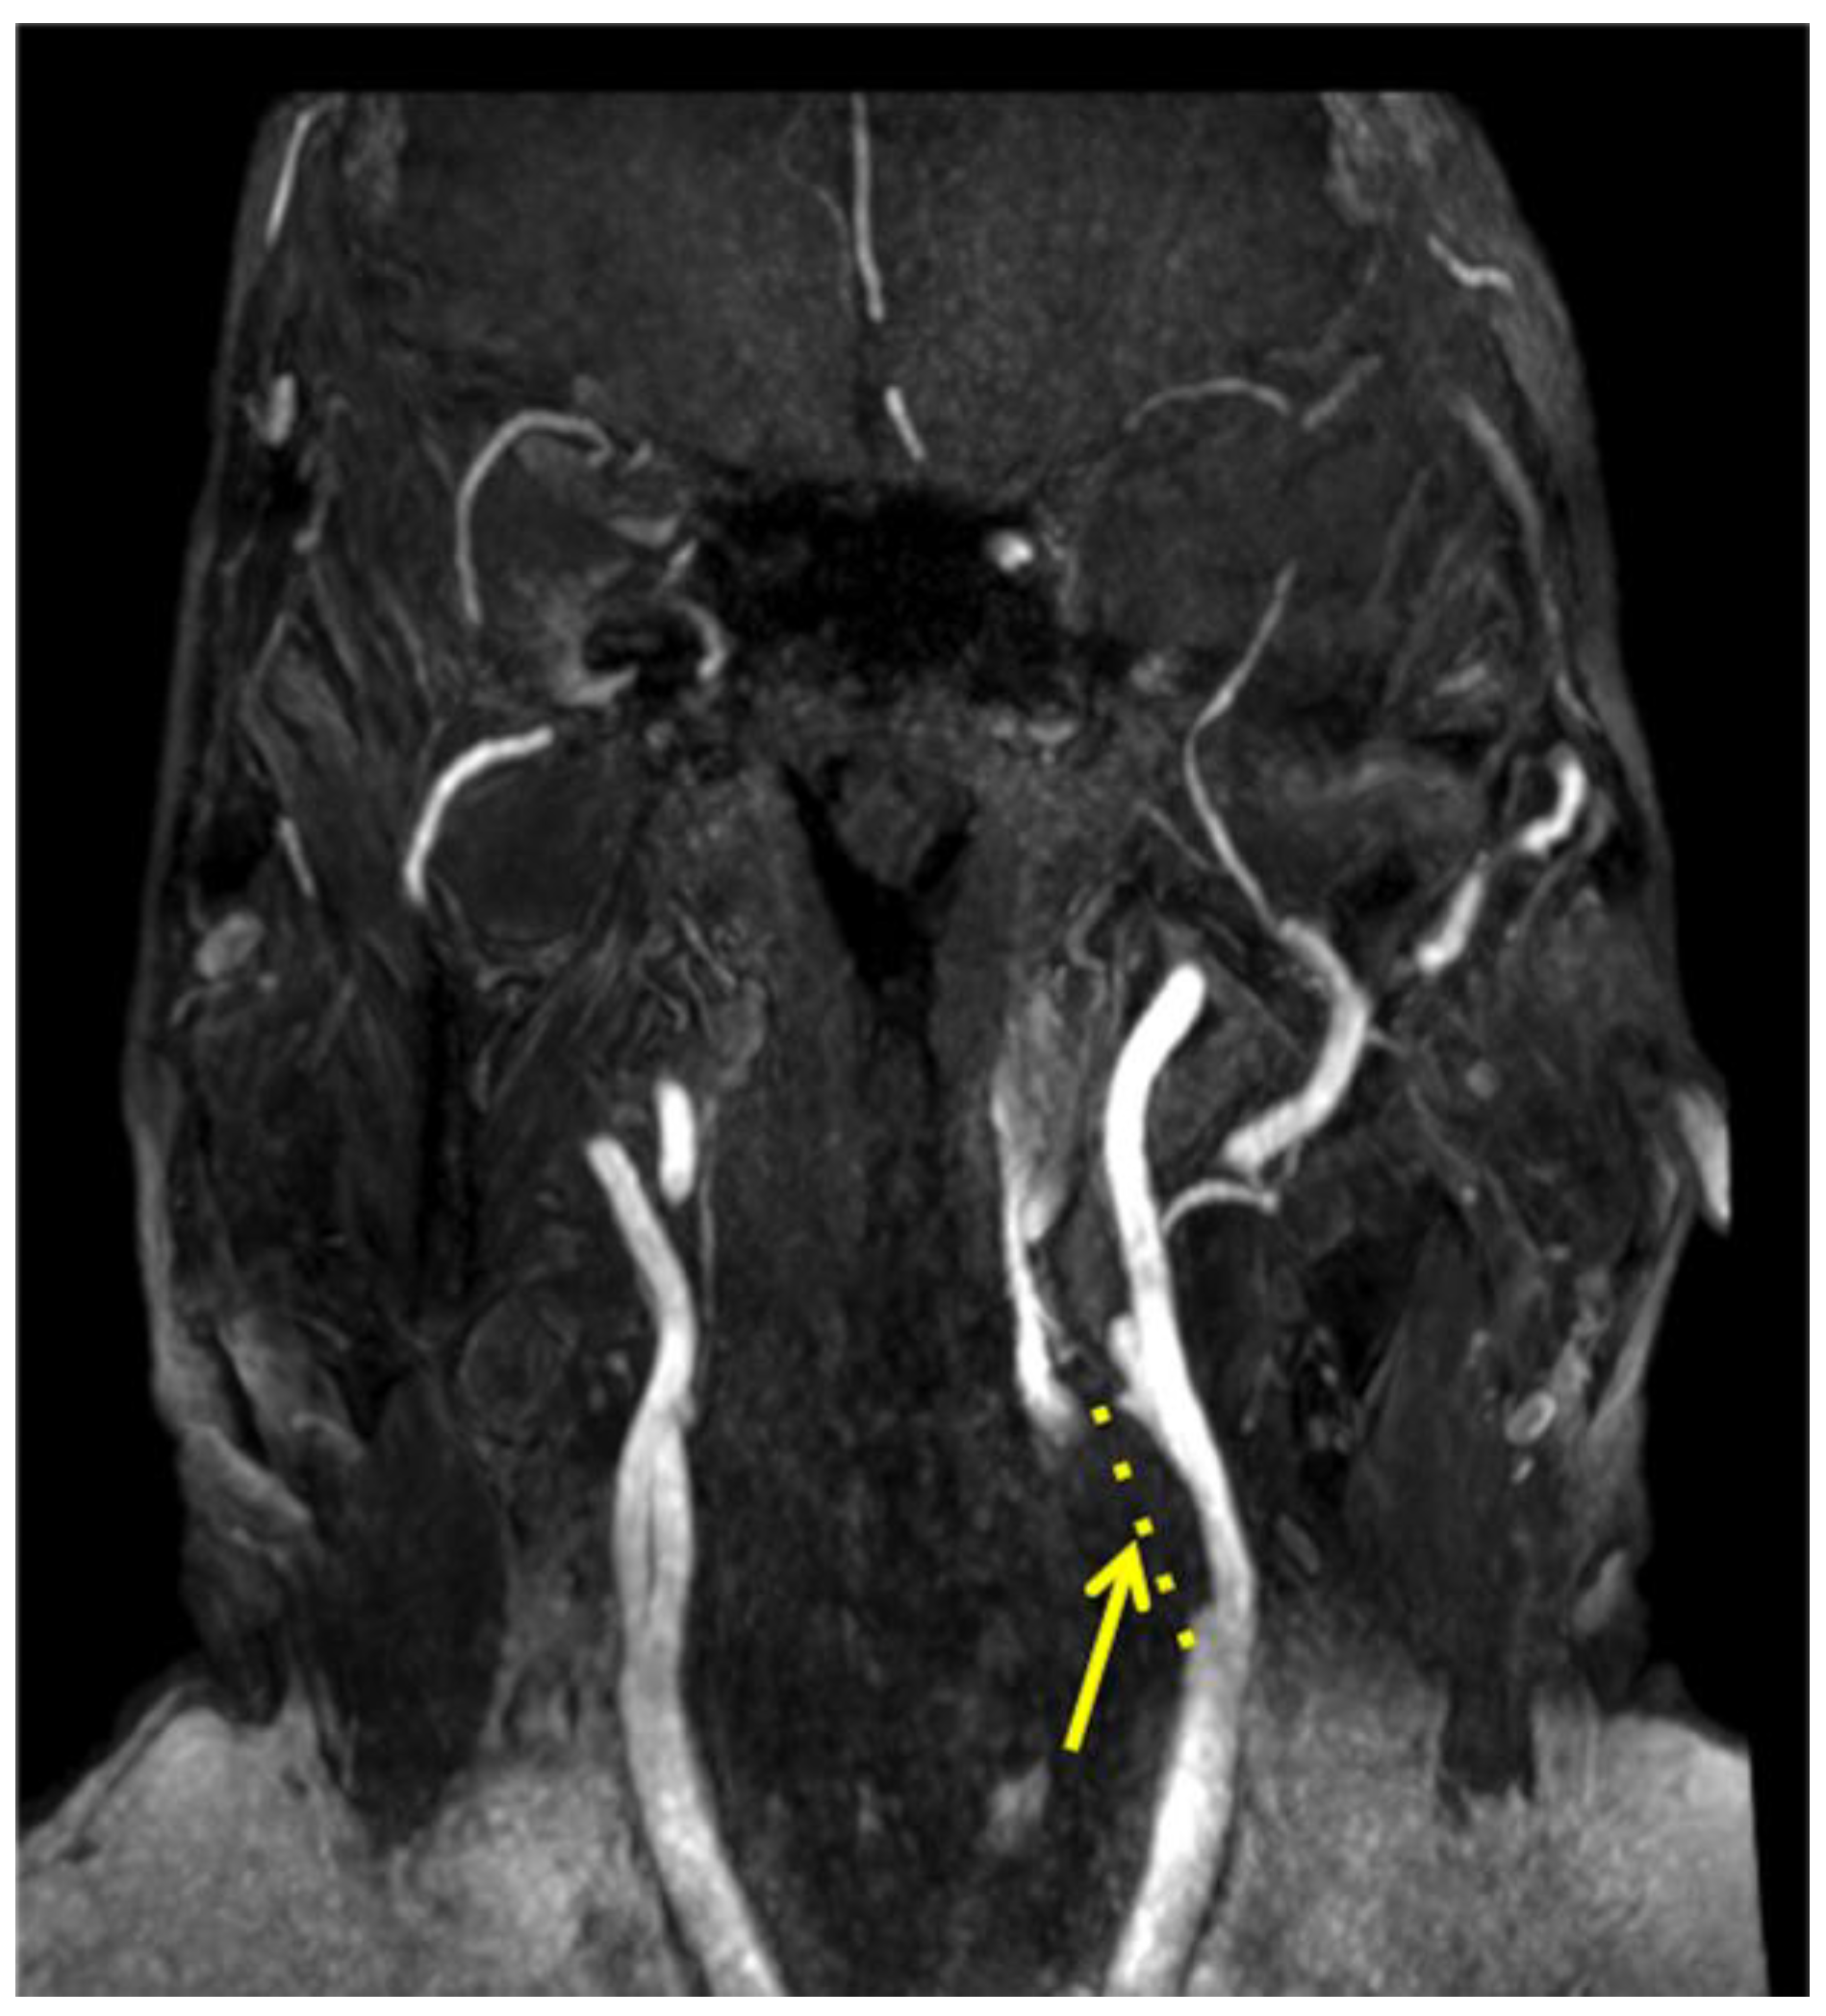

3. Computed Tomography Angiography (CTA) and Magnetic Resonance Angiography (MRA)